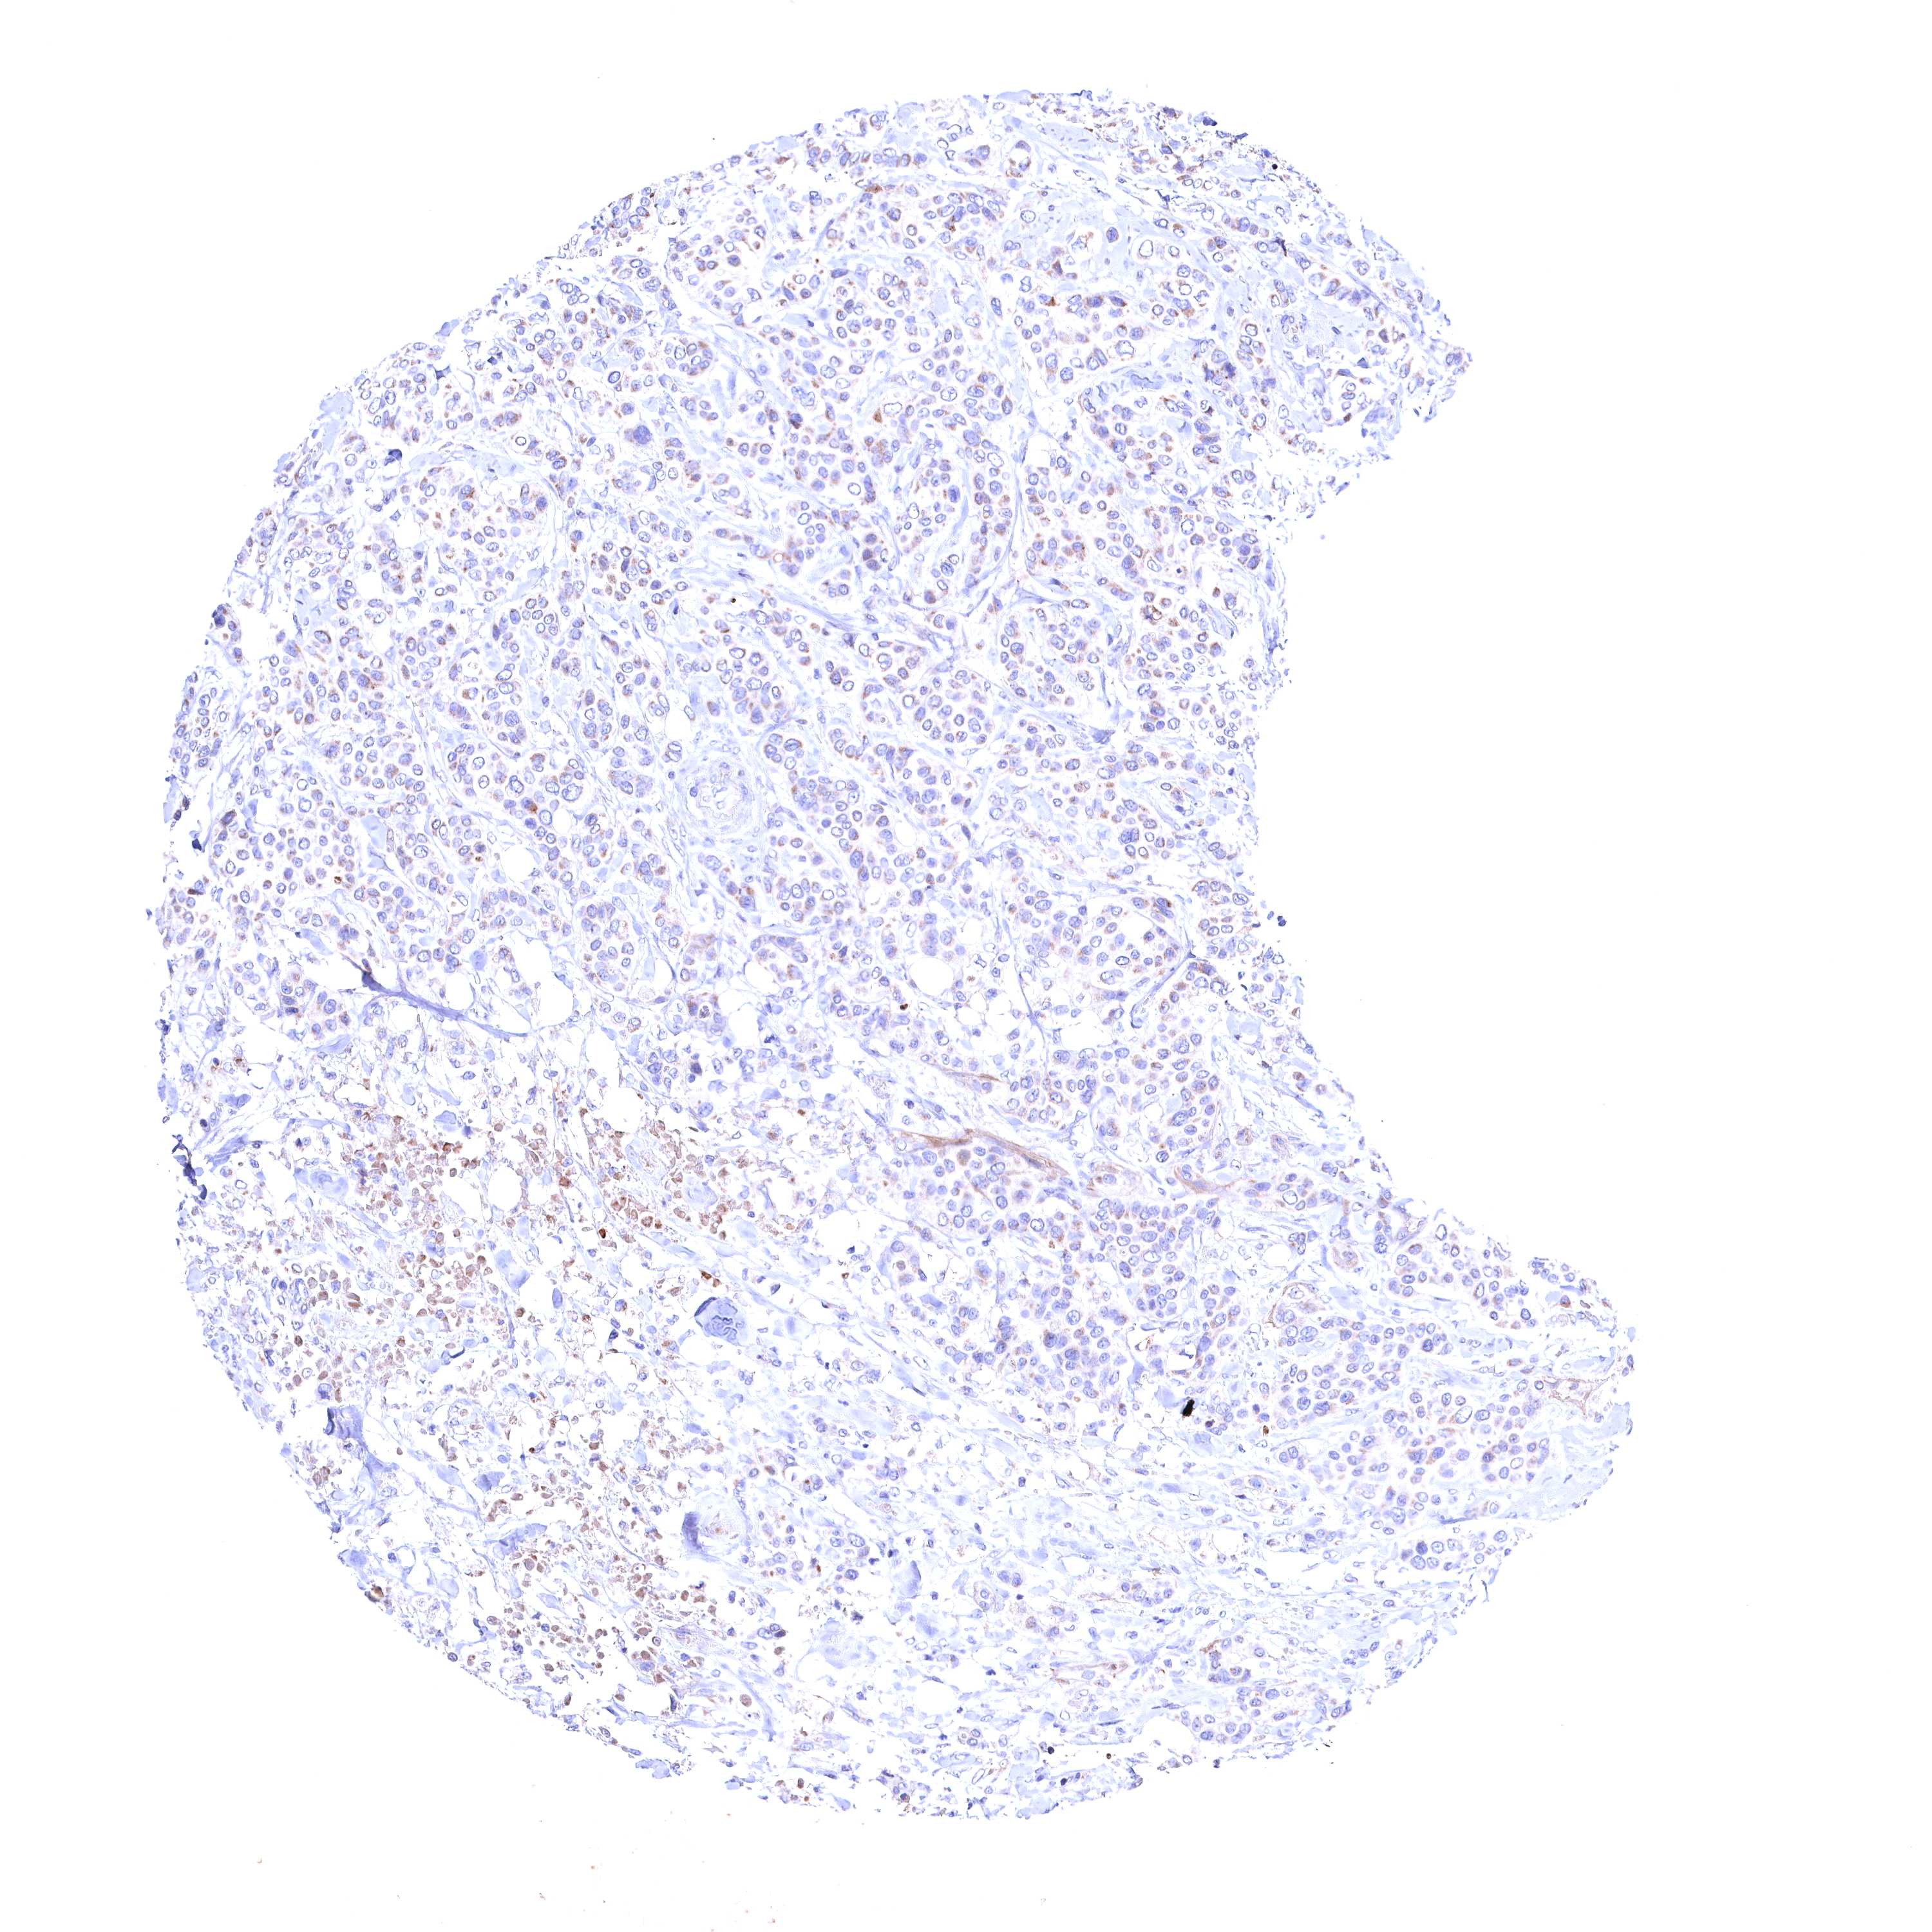

CANCER BREAST CANCER Show tissue menu

BRCA TCGA BRCA VALIDATION PROTEIN EXPRESSION